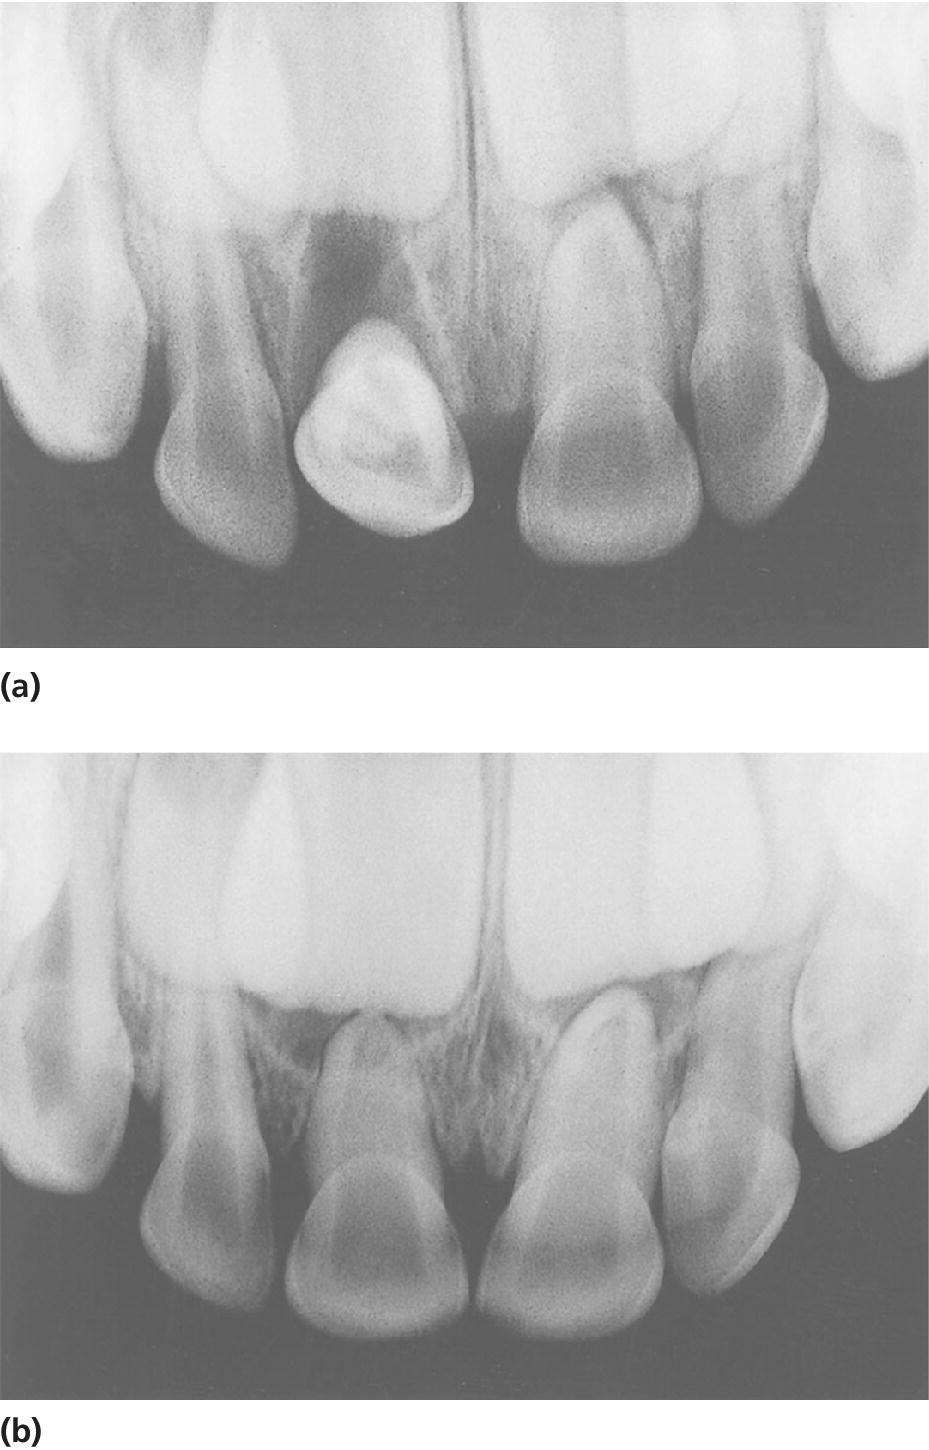

From pocketdentistry.com

18 Traumatic Dental Injuries Pocket Dentistry Tooth Decay Head Pressure A tooth infection or “tooth abscess” is a collection of pus and bacteria that forms inside the tooth or gum. If you notice tooth pain, especially. Dental problems like tooth decay, dental infections, or tooth fractures can cause headaches. Some conditions that can cause such pain, like sinus infections, are not related to a dental or primary headache disorder. For. Tooth Decay Head Pressure.